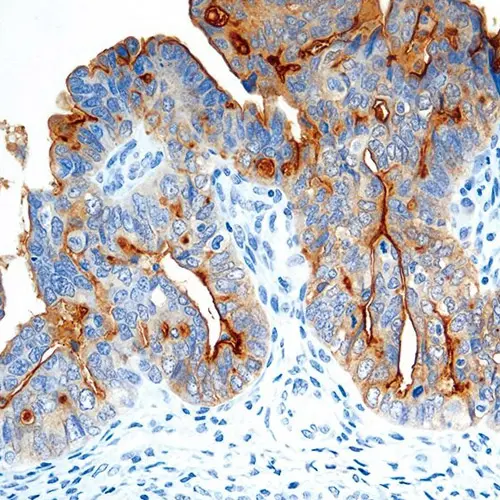

Ovarian tumor: immunohistochemical staining for Folate Receptor Alpha. Note intense cytoplasmic staining. Folate Receptor Alpha: clone BN3.2

Folate is a basic component of cell metabolism and DNA synthesis and repair. It is involved in essential one-carbon transfer reactions and is a vitamin required by both normal and tumor cells. Folate entry into cells is facilitated via two different systems: the reduced folate carrier, which utilizes a bidirectional anion-exchange mechanism, and the folate receptor system. Folate Receptor Alpha is a membrane-bound member of the folate receptor family, facilitating folate transport via a mechanism termed potocytosis where the receptor is internalized and then recycled back to the cell membrane. Staining patterns are both membranous and cytoplasmic due to this mechanism. Members of the folate receptor family share highly conserved sequences in the open reading frames, but differ in amino acids in the 5' untranslated regions and as a consequence can differ in function and tissue expression. Folate receptor alpha expression is reported to be highly restricted in normal tissues and only selectively overexpressed in a limited number of epithelial malignancies.